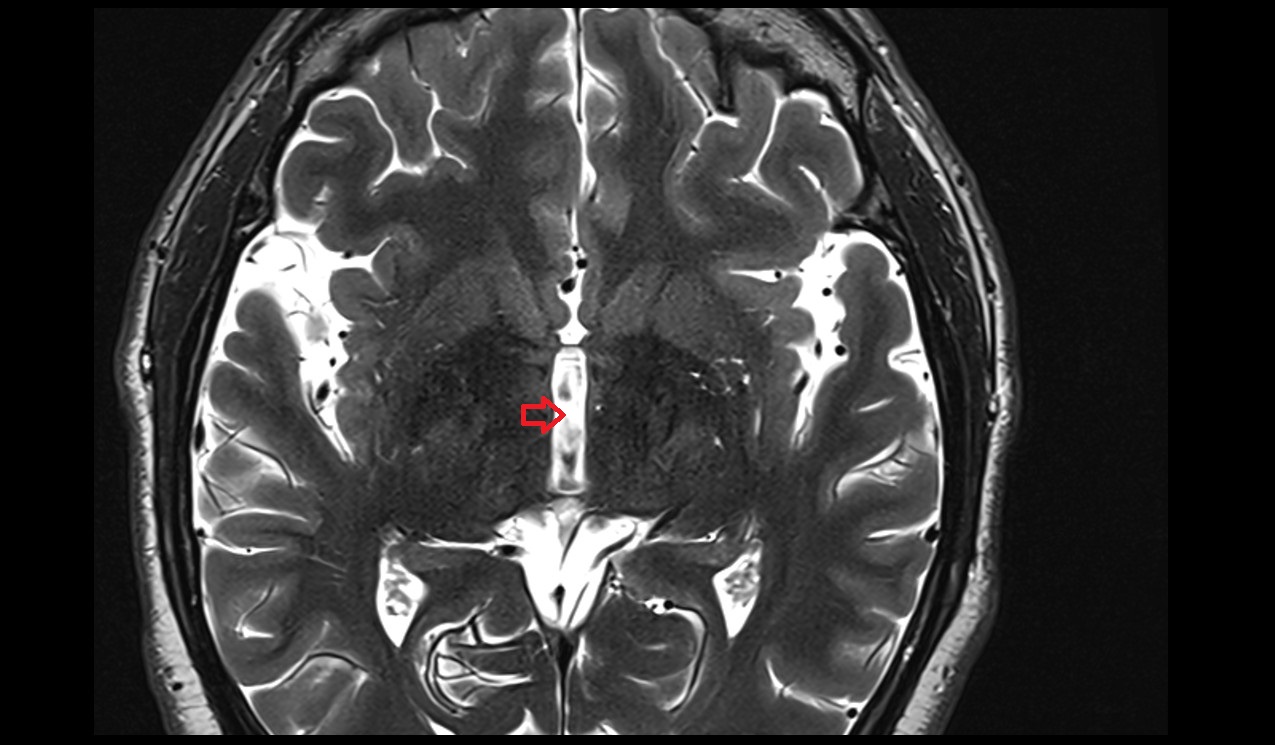

- Interthalamic adhesion

- Third ventricle